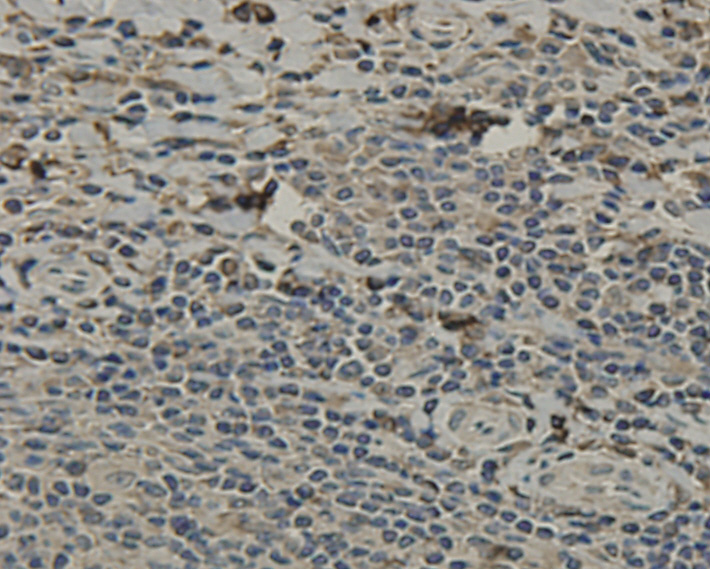

Immunohistochemical analysis of paraffin-embedded human pancreas tissue using anti-SCAI antibody. Counter stained with hematoxylin.

Immunohistochemical analysis of paraffin-embedded human tonsil tissue using anti-SCAI antibody. Counter stained with hematoxylin.

Immunohistochemical analysis of paraffin-embedded human lung tissue using anti-SCAI antibody. Counter stained with hematoxylin.

Immunohistochemical analysis of paraffin-embedded human liver tissue using anti-SCAI antibody. Counter stained with hematoxylin.

Immunohistochemical analysis of paraffin-embedded human brain tissue using anti-SCAI antibody. Counter stained with hematoxylin.

Immunohistochemical analysis of paraffin-embedded human heart tissue using anti-SCAI antibody. Counter stained with hematoxylin.